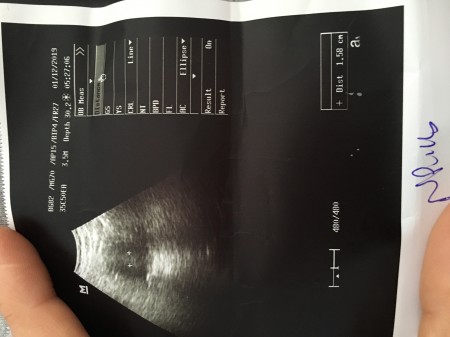

kızlar dun acıldekı ulturason goruntum

sordu

kızlar dun kanama oldum acıle gıttım progrstan verdı 100 ve 200 seklınde ılac dun kullandım hemem kanamam gectı betam suan 571.31 kese gorunmuyo dedı ama sızce nası kese olmadıgı ıcın kanama nıye oluyo anlamak zor dedı

Canım o işaretlediği kese saten dost yazıyor ya 1.58 cm benim de 6 hafta 2.25 cm mesela düşük t3hliken olmuş sen haplarını kullan acil de bilemiyorlar saten pek sen kadın doğum git kese işte o isaretledigi